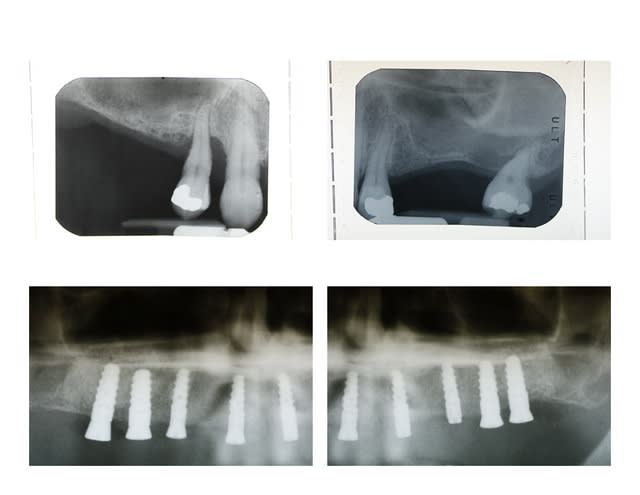

Tout à fait jeamba. Comme tu le dit très justement il n'est pas facile de pouvoir recouvrir la membrane recouvrant ton comblement à moins de :

1- faire un lambeau tracté coronairement (ce qui bride le vestibule et est préjudiciable au niveau antérieur)

2- ou bien faire un conjonctif enfoui (ou pédiculé palatin pour le maxillaire).

Une autre alternative est comme tu le dis d'extraire, d'attendre une cicatrisation des tissus mous (2 à 4 semaines) avant de passer au comblement.

J'ai également trouvé une autre alternative dont je n'ai vu personne d'autre utiliser. Comme vous êtes sympas je vous fait part de ce petit truc utile: prenons l'exemple présenté sur le photos ci jointe où une 22 fracturée doit être extraite. Le principe que j'ai mis au point est de meuler la 22 de facon à enfouir la racine à un niveau sous gingival, quaisiment juxta osseux et d'attendre quelques semaines avant de passer à l'extraction. Cela à pour conséquence un recouvrement radiculaire par les tissus gingivaux. Une fois la racine enfouie, je n'ai plus qu'à ouvrir, extraire au periotome, faire mon comblement si besoin, placer ma membrane et suturer mon lambeau sans avoir à le tracter, ou presque.